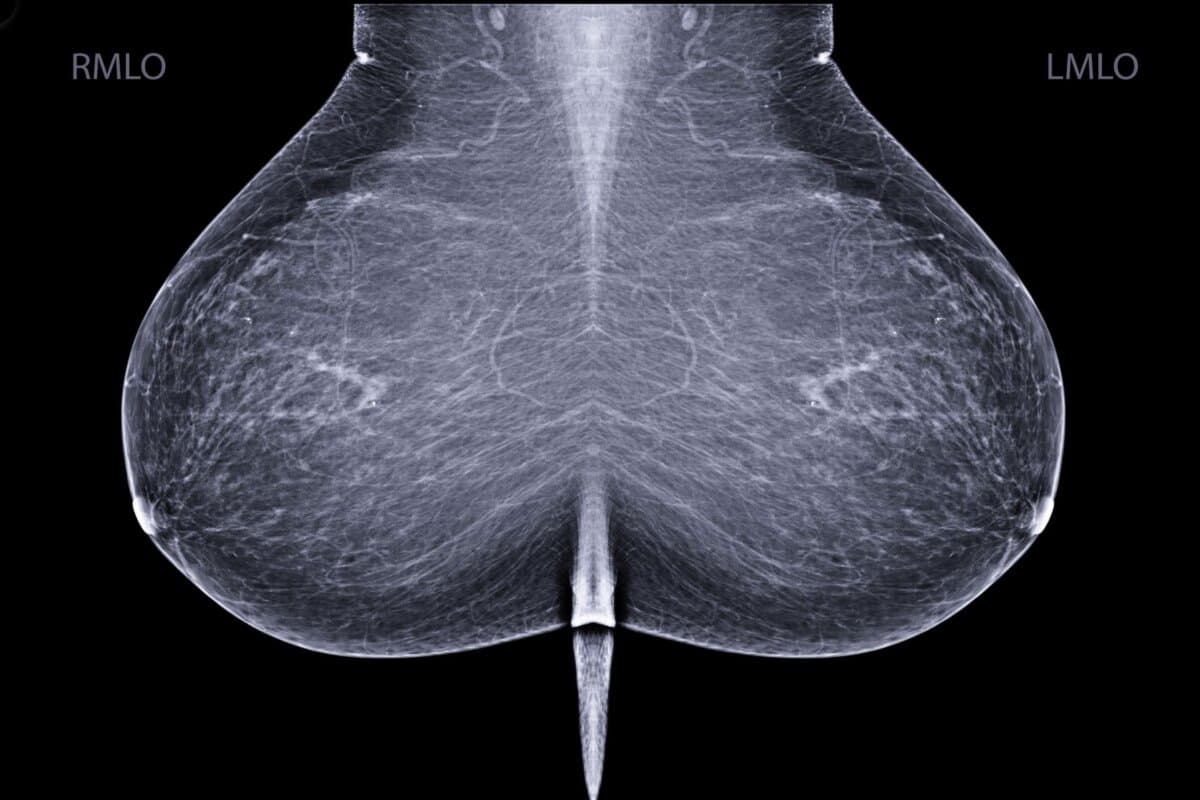

«Wir können mit erstaunlich hoher Genauigkeit vorhersagen, ob eine Frau in den nächsten ein bis fünf Jahren an Krebs erkranken wird, und zwar allein auf der Grundlage von lokalen Unterschieden zwischen ihrem linken und rechten Brustgewebe», sagt Jon Donnelly, (1) Autor der Studie im Journal Radiology (2).

AsymMirai orientiert sich nun an Gewebsunterschieden zwischen der linken und der rechten Brust, der «lokalen bilateralen Unähnlichkeit», die auchMirai verwendete, um Tumoren zu erkennen.